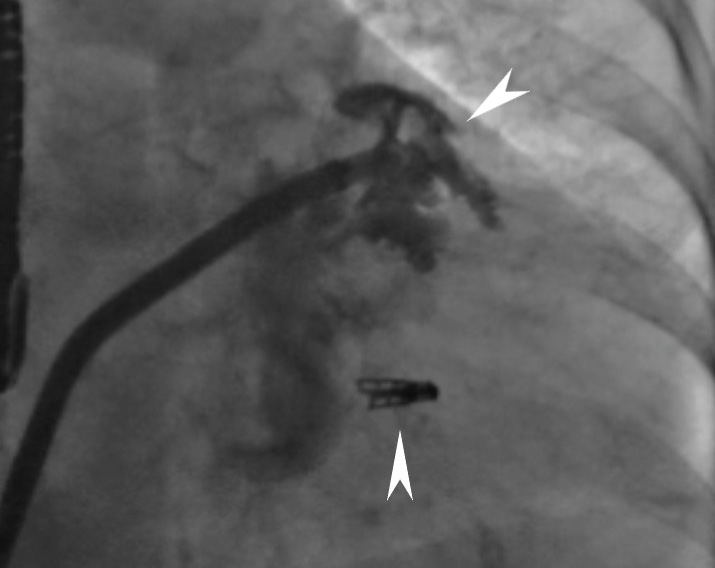

В связи с тяжелыми сопутствующими заболеваниями и высоким операционным риском принято решение о проведении малоинвазивной одномоментной операции. Под общей анестезией правым трансфеморальным доступом выполнена антеградная катетеризация нижней полой вены. На проводнике 0,035" в полость правого предсердия проведена система доставки иглы для транссептальной пункции. Под контролем чреспищеводной ЭхоКГ (ЧП ЭхоКГ) сделана пункция межпредсердной перегородки с последующим расширением пункционного отверстия. Игла для трансептальной пункции заменена на супержесткий проводник 0,035". Далее по проводнику в полость левого предсердия на 3 мм доставлен управляемый направляющий катетер для системы MitraClip 24 Fr. Под флюороскопическим и ЧП ЭхоКГ контролем клипса проведена и позиционирована в левом желудочке. Выполнен последовательный захват передней и задней створок МК. По данным ЧП ЭхоКГ достигнута оптимальная коаптация створок, регургитация до 1-й степени. Выполнено высвобождение клипсы MitraClip от системы доставки. На супержестком проводнике система доставки MitraClip (24 Fr) под контролем мануальной компрессии зоны чрескожного доступа заменена на систему доставки окклюдера Amulet (14 Fr). Выполнено контрастирование полости УЛП, далее в полость УЛП доставлен и имплантирован окклюдер Amplatzer Amulet 28 мм. При контрольной ЧП ЭхоКГ позиционирование окклюдера адекватное, раскрытие полное. Провокационная проба отрицательная, система доставки отцеплена. Доставочный интродьюсер извлечен, выполнен мануальный пассивный гемостаз, наложена асептическая давящая повязка. Касательно дезагрегантной и антикоагулянтной терапии, всего было введено 12 500 МЕ гепарина натрия, во время процедуры осуществлялось четырехкратное измерение ACT (activated clotting time – активированное время свертывания крови), целевые значения поддерживались в диапазоне 250–300 с. Вмешательство прошло без осложнений. Пациент экстубирован, переведен в отделение реанимации и интенсивной терапии для динамического наблюдения. Рентгенографический результат представлен на рис. 1, 2.

Рис. 2. Рентгенография после установки окклюдера Amulet в ушко левого предсердия. Визуализируется ранее установленная клипса MitraClip (указано стрелками)